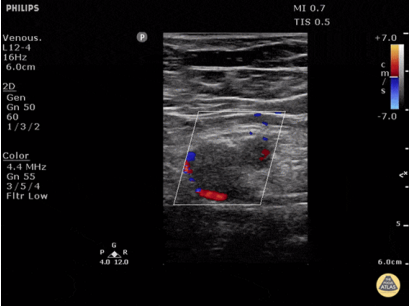

A线的出现代表胸膜线以下含气良好。此时针对呼吸困难的病因,就应考虑是否存在气道病变或血管病变。需要行下肢血管彩超进一步筛查,如果发现血管中有回声团(图2),考虑存在下肢静脉血栓,此时需要警惕肺栓塞的可能。如有条件,可行肺动脉CTA检查;如无条件,可检查凝血功能、心肌标志物、心脏彩超等进行筛查。如果下肢血管彩超没有问题,就要加做PLAPS点(图3),即最常出现胸腔积液、炎性变之处,若此处正常,考虑可能是气道疾病,若出现胸膜下斑片影、实变影,考虑肺炎可能。(3)不论有无胸膜滑动征,如果在患者一侧以A线为主,另一侧以B线为主(AB profile)(图4),考虑为肺炎;若超声有实变征象(C profile)(图5),则更支持肺炎的诊断。图4 一侧为A线,另一侧为B线(AB profile)(4)如果胸膜滑动征消失,且观察到B线(B’ profile)(图6),此种情况考虑肺炎。(5)如果胸膜滑动征消失,且双肺表现为A线,称为A'profile。